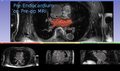

In the left image below (Figure R2), the manual segmentation of the endo-cardium is overlaid on the pre-op MRI. In the right image below (Figure R3), the same manual segmentation of the endo-cardium (of the pre-op MRI) is overlaid on the registered post-op MRI. This shows the registration accuracy around the endo-cardium region, which is the region of interest.